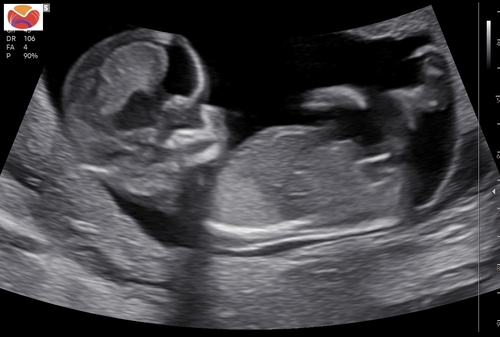

Een jongen! 馃挋 nub wijst flink omhoog.

Het bovenste streepje is denk ik de navelstreng en dat onderste streepje daar pas je de nubtheorie op toe. Dat onderste streepje wijkt wel iets af naar boven dus in deze zou je kunnen zeggen hey word een jongen. Bij een meisje schijnt hey echt horizontaal te liggen maargoed het is maar een theorie

Onder de navelstreng zie je inderdaad dat de nub naar boven wijst. Plaats je foto ook eens in het algemene nub theorie topic :) weet zeker dat je alleen 馃挋馃挋馃挋 krijgt 馃グ